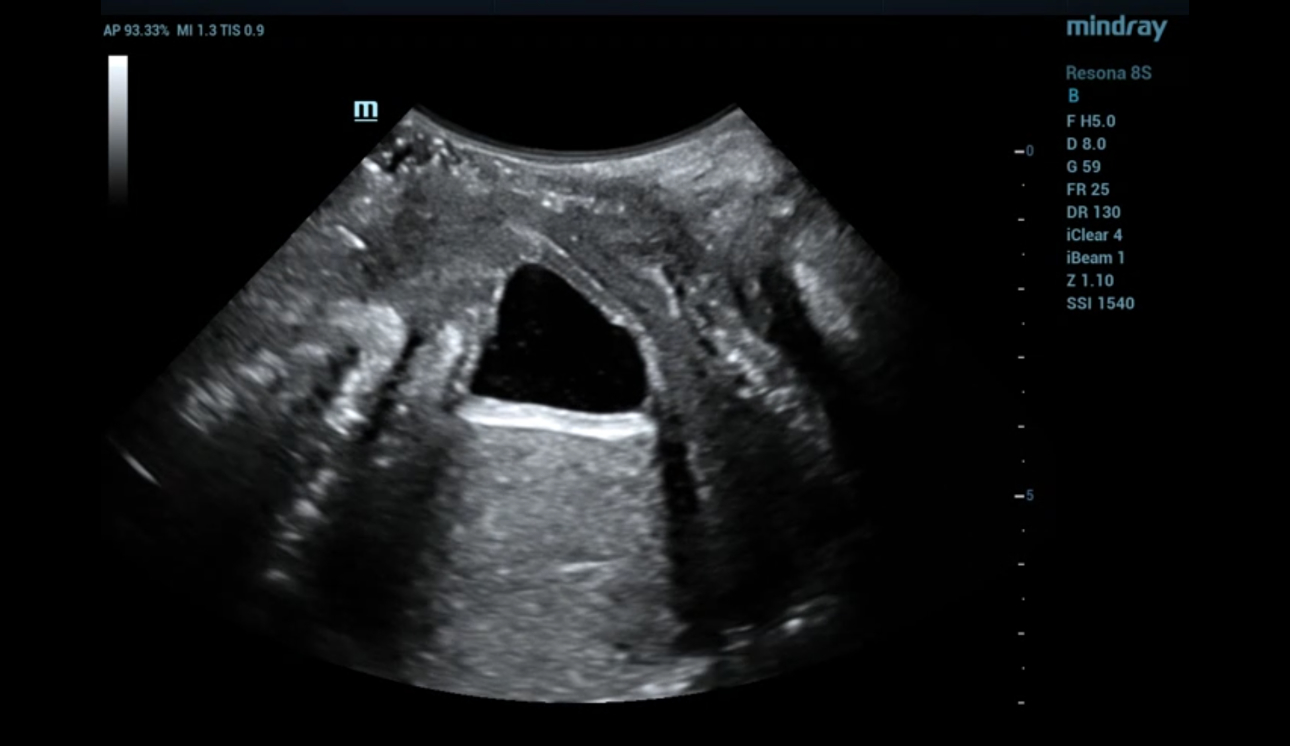

levator-trauma-fig5-pc

형상 3. 좌측 avulsion의 볼륨 이미징

levator-trauma-fig6-pc

형상 4. 좌측 avulsion의 Ipage+ 이미지